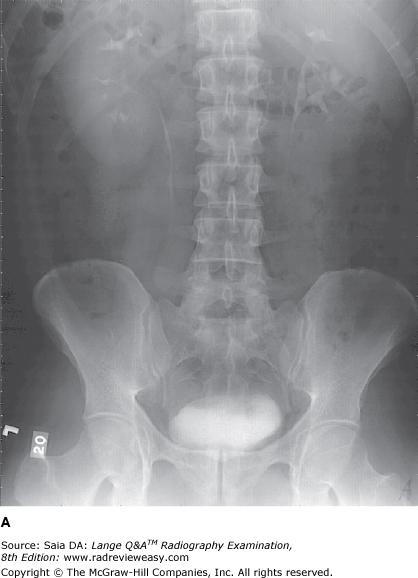

The number 1 in the radiograph in Figure A represents which of the following renal structures?

B Renal pelvis

-The pictured radiograph is one of a series of IVU (IU) images. It was done prone at 20 minutes after injection of the contrast medium. The urinary collecting system is well demonstrated. The renal pelvis(number 1) is the proximal expanded end of the ureter lying within the renal sinus. The minor calyces(number 3) receive urine from the collecting tubules of the renal pyramids and convey it to the major calyces (number 2), which empty into the renal pelvis. Urine is carried down the ureters by peristaltic waves.